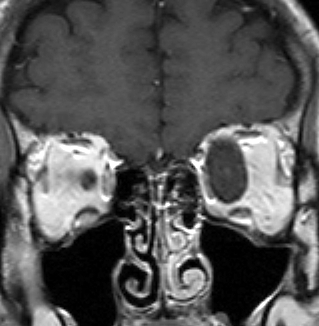

- 子供に見られる視神経膠腫は頻度の高いもので,NF-1の4%に発生します

- 下の図のように眼窩の中の視神経が腫瘍になることもありますし,視神経交叉といって両方の視神経が合わさった場所にできるものもあります。視神経膠腫はとても小さい子供にできて視力が下がりますが,手術で摘出することはできません。でも,とってもゆっくり大きくなり,ある程度の年齢になると大きくなるのが止まってしまいます。手術以外の治療法は毛様細胞性星細胞腫(クリック)のところに書いてありますから読んで下さい。